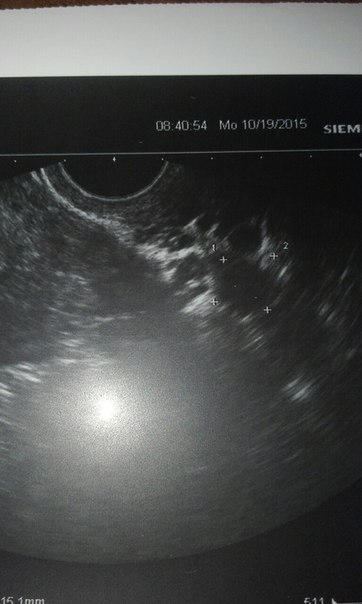

Сходила на узи..Фолликулометрия

Всем привет)Ну вот наконец то я сходила на фоликулометрию)ДФ 15 мм..10 дц сегодня..Сказала придти через неделю..Посмотрит что дальше!

Все в порядке..Эндометрий 15 мм..Не многоват ли?До О сказала дней 5...Ну так и получается на 15 дц..Выписала таблетки..Фемибион и окситоцин..Кому помогли?Узист сказала для того чтоб фолик лопнул..